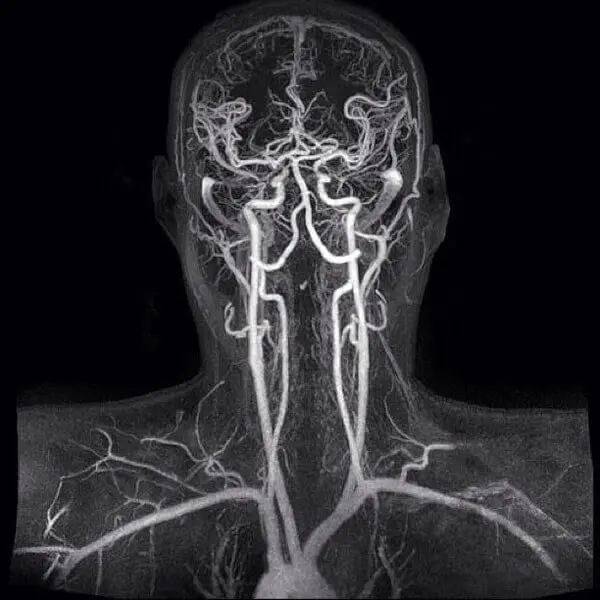

Малюнок – МРТ судин шиї та голови.

МРТ реконструкція судин голови і шиї дозволяє виявити слабкі місця в кровопостачанні мозку. Іншими словами – ділянки мозку з дефіцитом кровопостачання через патологію судин. Як показує наша багаторічна практика, це може бути недорозвинення (звуження або повна відсутність) деяких судин у мозку. Наприклад, в задньому сегменті так званого судинного Віллізеєва кола (центр з’єднання декількох магістральних артерій в мозку), такі зміни зустрічаються у 24,5% людей. Ця цифра встановлена H.Yasargil (Німеччина) і приведена Piter Duus в 1997.

Віллізеєве судинне коло – це місце злиття чотирьох головних артерій головного мозку. Така будова судин мозку була передбачена природою для підстраховки: якщо одна артерія виходить з ладу (частіше на шиї), то кровотік компенсується за рахунок інших трьох артерій.

Для розуміння причини запаморочення або головного болю важливо побачити ті судини, які звужені або які зовсім не працюють. Як було сказано вище, мозок харчується чотирма великими артеріями. Ці судини проходять через шию, входять в порожнину черепа і утворюють Веллізеєве коло і далі судини починають галузиться.

На МРТ видно не тільки великі, але більш дрібні артерії мозку.

Можна побачити відсутність (нерозвиненість) або звуження (недорозвинення, спазм) однієї з артерій. Такі зміни в судинах можуть викликати збій функції ділянки мозку. У тому числі ділянки, від якої залежить запаморочення або головний біль.

Зображення судин при МРТ виходить за рахунок оцінки апаратом руху крові в судині. Принцип МРТ діагностики – це оцінка різних фізичних станів рідини. Кров – це рухома рідина з іншими фізичними характеристиками, ніж тканини мозку. Тому за допомогою МРТ ми можемо оцінити не тільки стан мозку, а й стан судин. Спеціальні програми МРТ апарату «ловлять» потік крові в судинах, запам’ятовують цей сигнал і передають інформацію в свій МРТ-комп’ютер. Там інформація обробляється і виводиться на екран у вигляді зображення мережі всіх судин мозку (див. нижче).

Отримане зображення – тривимірне. Його можна покрутити за допомогою мишки в трьох площинах і, таким чином, простежити хід будь-якої судини головного мозку. Судину видно на всьому своєму протязі. У неї можна виявити звуження (спазм, атеросклероз, недорозвинення) або розширення (аневризма).